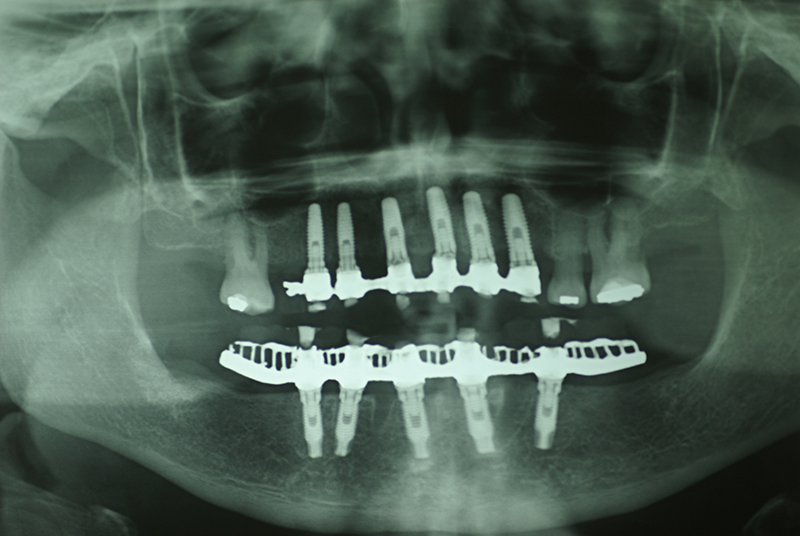

- Planejamento Digital: Com o auxílio de tecnologias como tomografias e softwares 3D, a posição dos implantes é planejada com precisão.

- Cirurgia de Instalação dos Implantes: Os implantes são fixados no osso maxilar ou mandibular, proporcionando uma base sólida para a prótese.

- Preservação óssea: A técnica estimula o osso, prevenindo sua reabsorção, comum em casos de perda dentária.